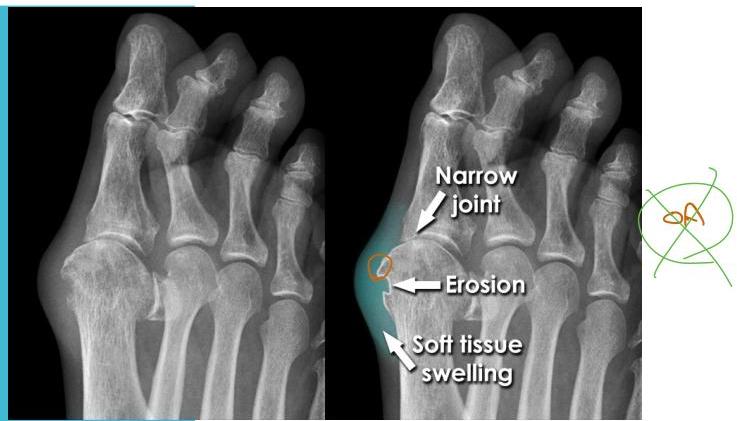

Rheumatoid Arthritis Pain vs. Osteoarthritis Pain

Rheumatoid arthritis